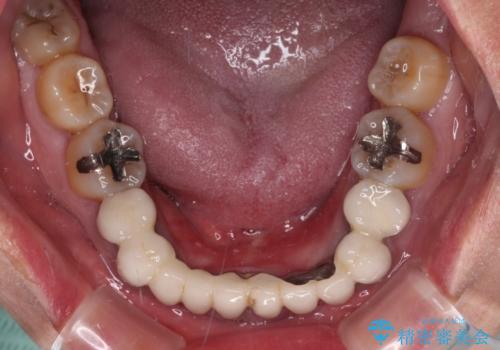

- 常に外れている下顎のブリッジと、前歯のデコボコと色を気にして来院された患者様です。

前歯のデコボコおよび奥歯の咬み合わせを改善するために、上顎左右の小臼歯を欠損スペースを利用して歯列を整え、矯正治療後に気になる上下前歯などをオールセラミッククラウンで美しく仕上げていくこととしました。

色や歯列が整ったことはもちろん満足いただけましたが、上顎の舌側転位していた前歯が綺麗に整ったことで違和感が減ったことを非常に喜んでいらっしゃいました。